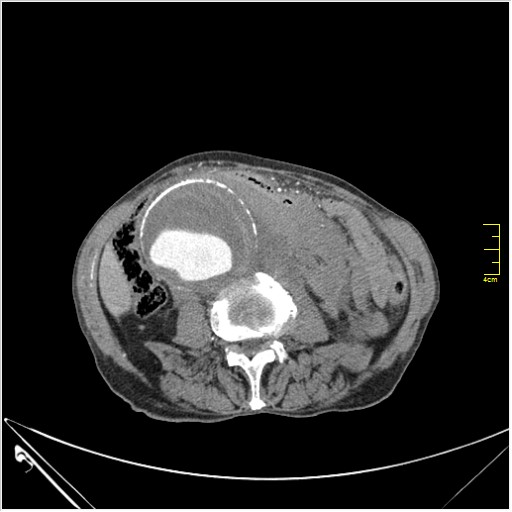

КТ брюшной полости. Мужчина с пальпируемой опухолью в животе

Пациент Т. 64 года, обратился на КТ брюшной полости амбулаторно (!), по направлению семейного врача с диагнозом abdominal mass, буквально: образование брюшной полости.

Uzgraph писал(а):Случай интересный - ногу сломишь. Вроде бы анефризма брюшной аорты(особенно по УЗИ), но что тогда за образования сидят на левой почке - онкология?

ИМХО простые кисты.